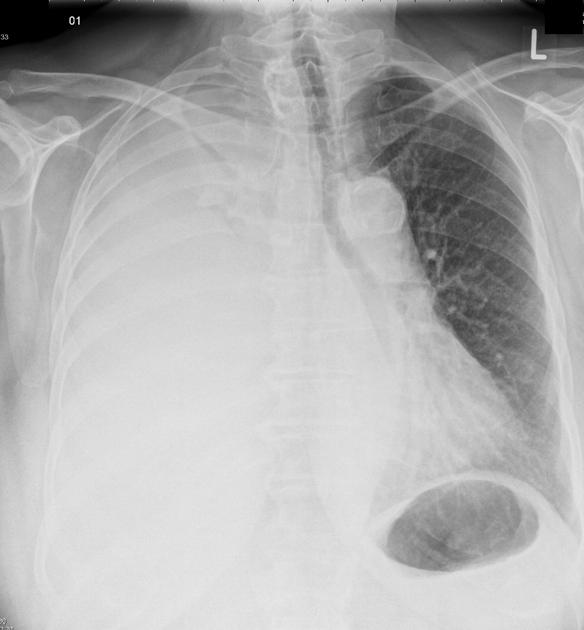

Approximate pleural effusion volume on chest X-ray (upright PA) — rough reference (Written February 23, 2026)